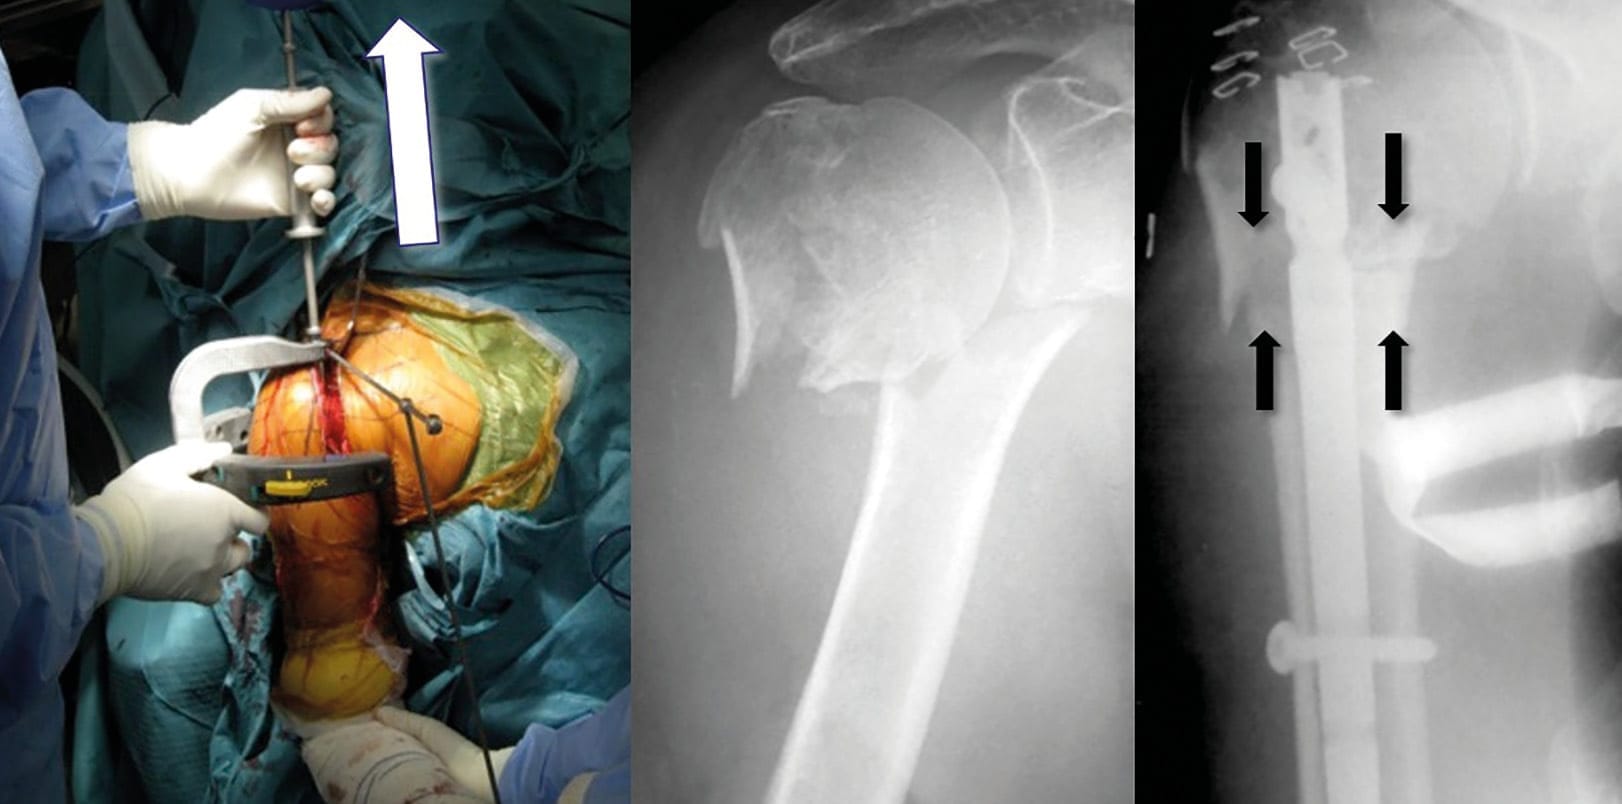

The clinical contributions center on knee arthroplasty and perioperative management. Two articles address surgical precision: trochlear sulcus modeling for femoral implant positioning during navigated TKA and conventional navigation with the extension gap first technique for proper bone cuts in TKA. The influence of audiovisual information on preoperative expectations in total knee replacement is also examined. Further contributions address multiligament knee injuries and gait analysis and the surgical classification and outcomes of third-generation percutaneous intramedullary nailing for displaced two-part surgical-neck fractures.